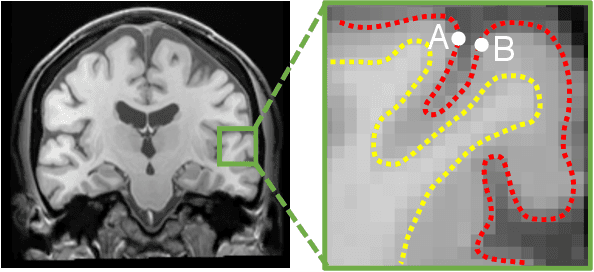

Abstract:Surface-based analysis of the cerebral cortex is ubiquitous in human neuroimaging with MRI. It is crucial for cortical registration, parcellation, and thickness estimation. Traditionally, these analyses require high-resolution, isotropic scans with good gray-white matter contrast, typically a 1mm T1-weighted scan. This excludes most clinical MRI scans, which are often anisotropic and lack the necessary T1 contrast. To enable large-scale neuroimaging studies using vast clinical data, we introduce recon-all-clinical, a novel method for cortical reconstruction, registration, parcellation, and thickness estimation in brain MRI scans of any resolution and contrast. Our approach employs a hybrid analysis method that combines a convolutional neural network (CNN) trained with domain randomization to predict signed distance functions (SDFs) and classical geometry processing for accurate surface placement while maintaining topological and geometric constraints. The method does not require retraining for different acquisitions, thus simplifying the analysis of heterogeneous clinical datasets. We tested recon-all-clinical on multiple datasets, including over 19,000 clinical scans. The method consistently produced precise cortical reconstructions and high parcellation accuracy across varied MRI contrasts and resolutions. Cortical thickness estimates are precise enough to capture aging effects independently of MRI contrast, although accuracy varies with slice thickness. Our method is publicly available at https://surfer.nmr.mgh.harvard.edu/fswiki/recon-all-clinical, enabling researchers to perform detailed cortical analysis on the huge amounts of already existing clinical MRI scans. This advancement may be particularly valuable for studying rare diseases and underrepresented populations where research-grade MRI data is scarce.

Abstract:Surface analysis of the cortex is ubiquitous in human neuroimaging with MRI, e.g., for cortical registration, parcellation, or thickness estimation. The convoluted cortical geometry requires isotropic scans (e.g., 1mm MPRAGEs) and good gray-white matter contrast for 3D reconstruction. This precludes the analysis of most brain MRI scans acquired for clinical purposes. Analyzing such scans would enable neuroimaging studies with sample sizes that cannot be achieved with current research datasets, particularly for underrepresented populations and rare diseases. Here we present the first method for cortical reconstruction, registration, parcellation, and thickness estimation for clinical brain MRI scans of any resolution and pulse sequence. The methods has a learning component and a classical optimization module. The former uses domain randomization to train a CNN that predicts an implicit representation of the white matter and pial surfaces (a signed distance function) at 1mm isotropic resolution, independently of the pulse sequence and resolution of the input. The latter uses geometry processing to place the surfaces while accurately satisfying topological and geometric constraints, thus enabling subsequent parcellation and thickness estimation with existing methods. We present results on 5mm axial FLAIR scans from ADNI and on a highly heterogeneous clinical dataset with 5,000 scans. Code and data are publicly available at https://surfer.nmr.mgh.harvard.edu/fswiki/recon-all-clinical